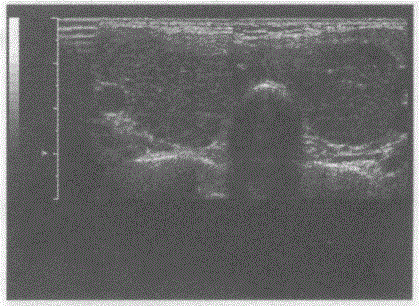

问题 临床资料:女性,25岁,自述心悸,多汗,食欲亢进,体重减轻6个月余,发现颈部增粗1周。 临床物理检查:甲状腺对称性增大,随吞咽上下运动,听诊有血管杂音。 超声综合描述:双侧甲状腺增大,回声减低,明显不均,内未见囊实性肿物,CDFI:内可见丰富动静脉血流信号,呈"火海"征。见下图及彩图。 {图1} 超声提示:

选项 A.结节性甲状腺肿 B.毒性甲状腺肿(原发性甲状腺功能亢进) C.甲状腺腺瘤 D.甲状腺正常声像图

答案 B